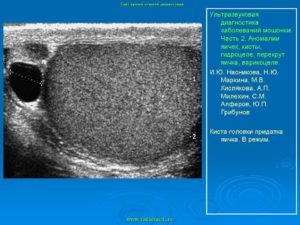

Кистозные новообразования яичка и его придатка

Семенные кисты (сперматоцеле) могут быть врожденными и приобретенными. Врожденная киста чаще маленьких размеров, жидкость внутри прозрачная. Приобретенные семенные кисты возникают из-за воспаления или травматизации, благодаря которым произошла закупорка протока с появлением кисты. По данным УЗИ мошонки киста выглядит, как образование округлой формы, с ровным, четким контуром, анэхогенной структуры.